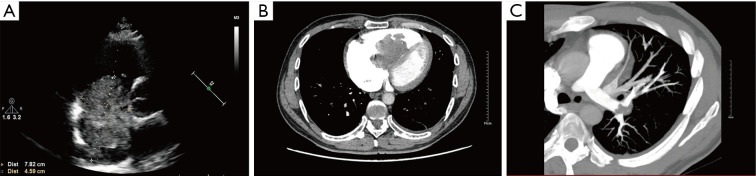

Case description: A 43-year-old man presented with progressive dyspnea, fatigue, and palpitations, imaging revealed a large mobile right atrial myxoma (78 mm × 52 mm) causing intermittent tricuspid valve obstruction and multifocal pulmonary emboli. Laboratory tests showed elevated B-type natriuretic peptide (BNP) and D-dimer levels. The patient was diagnosed with a benign cardiac tumor, PE, and New York Heart Association (NYHA) Class III heart function. Open-chest surgery with cardiopulmonary bypass resulted in successful tumor resection and emboli extraction. Postoperatively, the patient showed significant symptom improvement and no tumor recurrence at the 6-month follow-up. It is such giant right atrial myxomas that speak for the need for early diagnosis with surgical intervention.